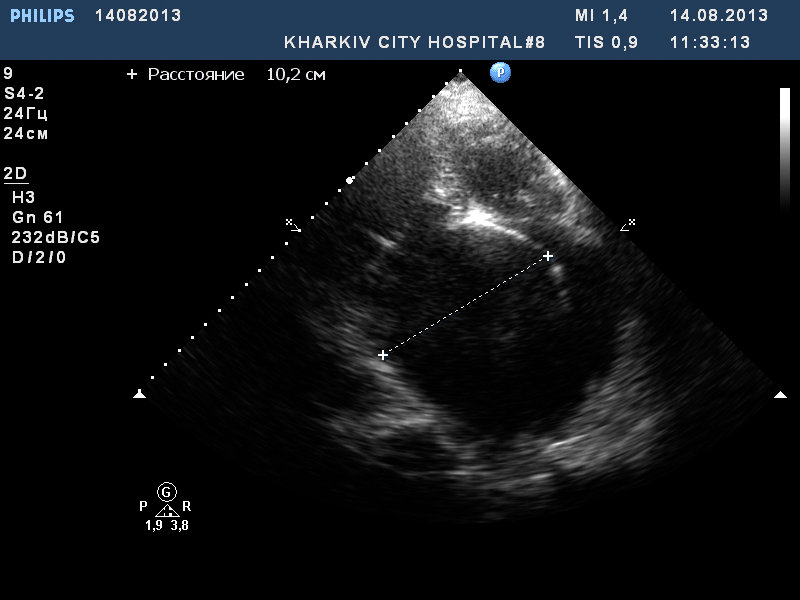

Митральный стеноз

Только что смотрел пациентку 82 года. Не было много времени, потому немного видео и фото. Удивил размер левого предсердия - 10.см.

В полости ЛП визуализируется спонтанное контрастирование тока крови.

Это точно левое предсердие?

Я смотрю в зеркальном отображении (не классически) . Левый желудочек по левую руку, правый по правую. Кстати правое предсердие в 10 см я не видел. А вы что подумали?

Спросил из-за толщины стенки ПЖ и уровня отхождения створок МК и ТК

Уровень отхождения створок стандартный. Просто из-за растянутого ЛП выглядит "необычно". Но и такой размер ЛП тоже "необычный".